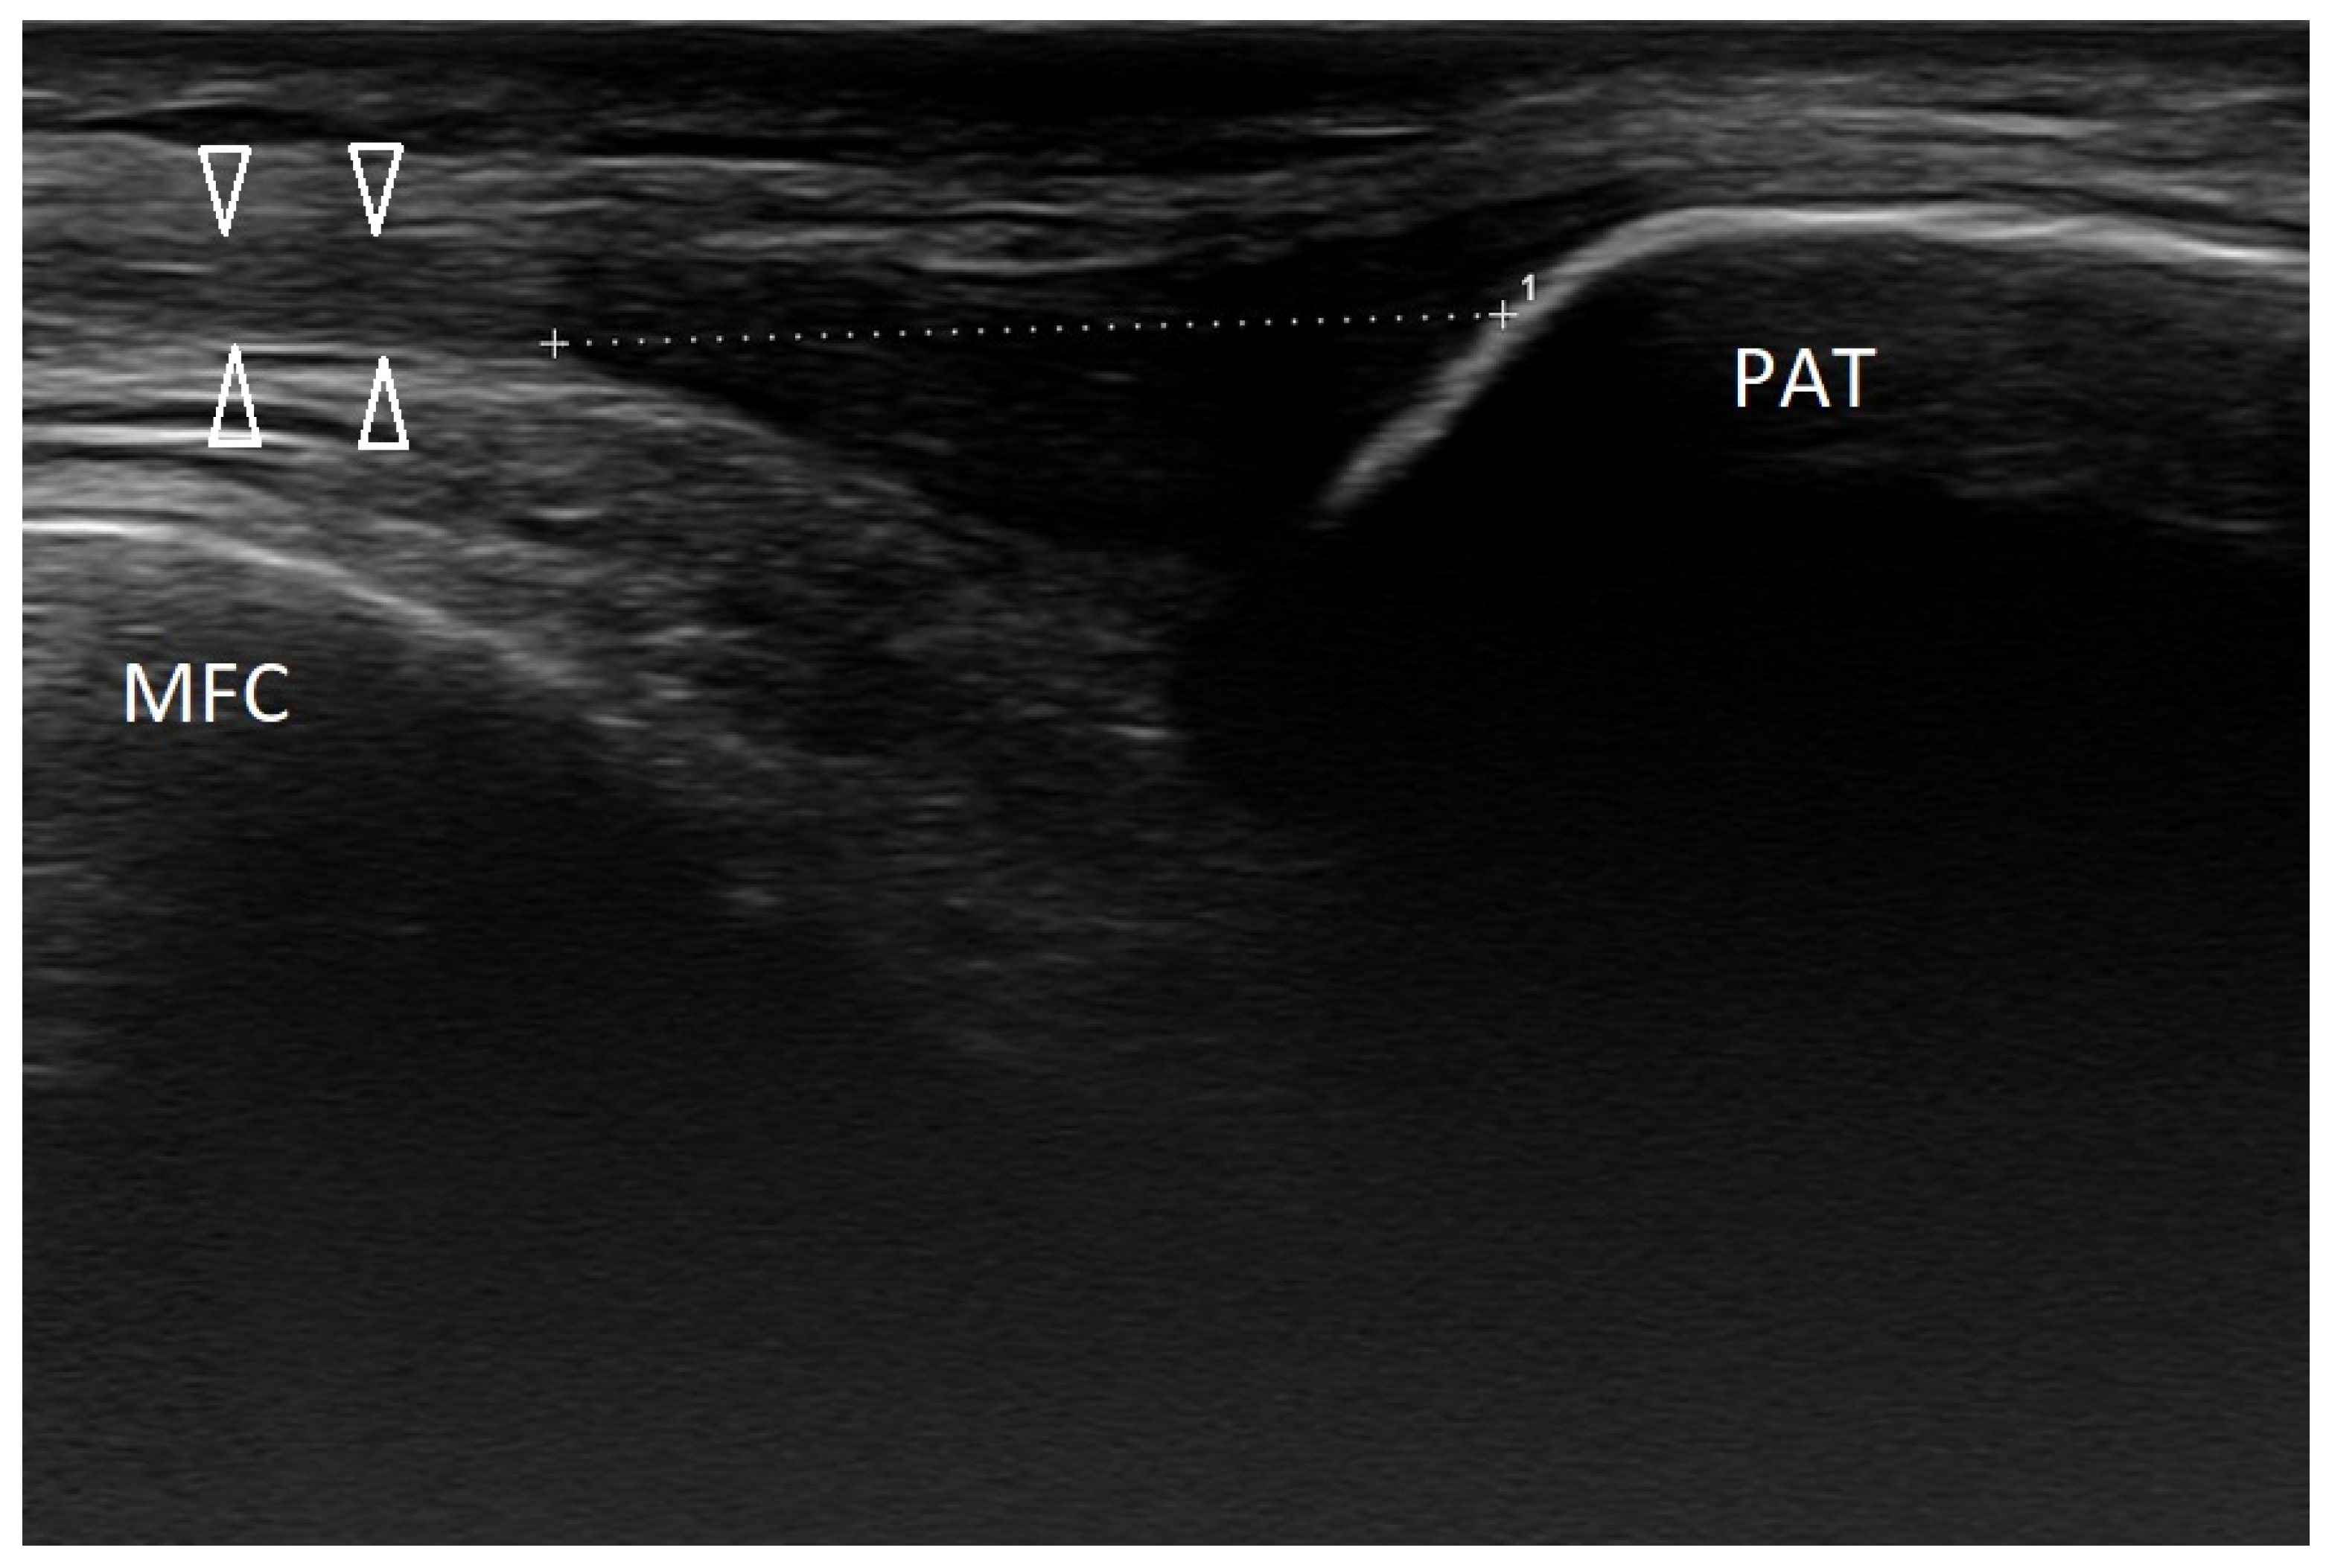

3.2.2. Osgood–Schlatter Disease